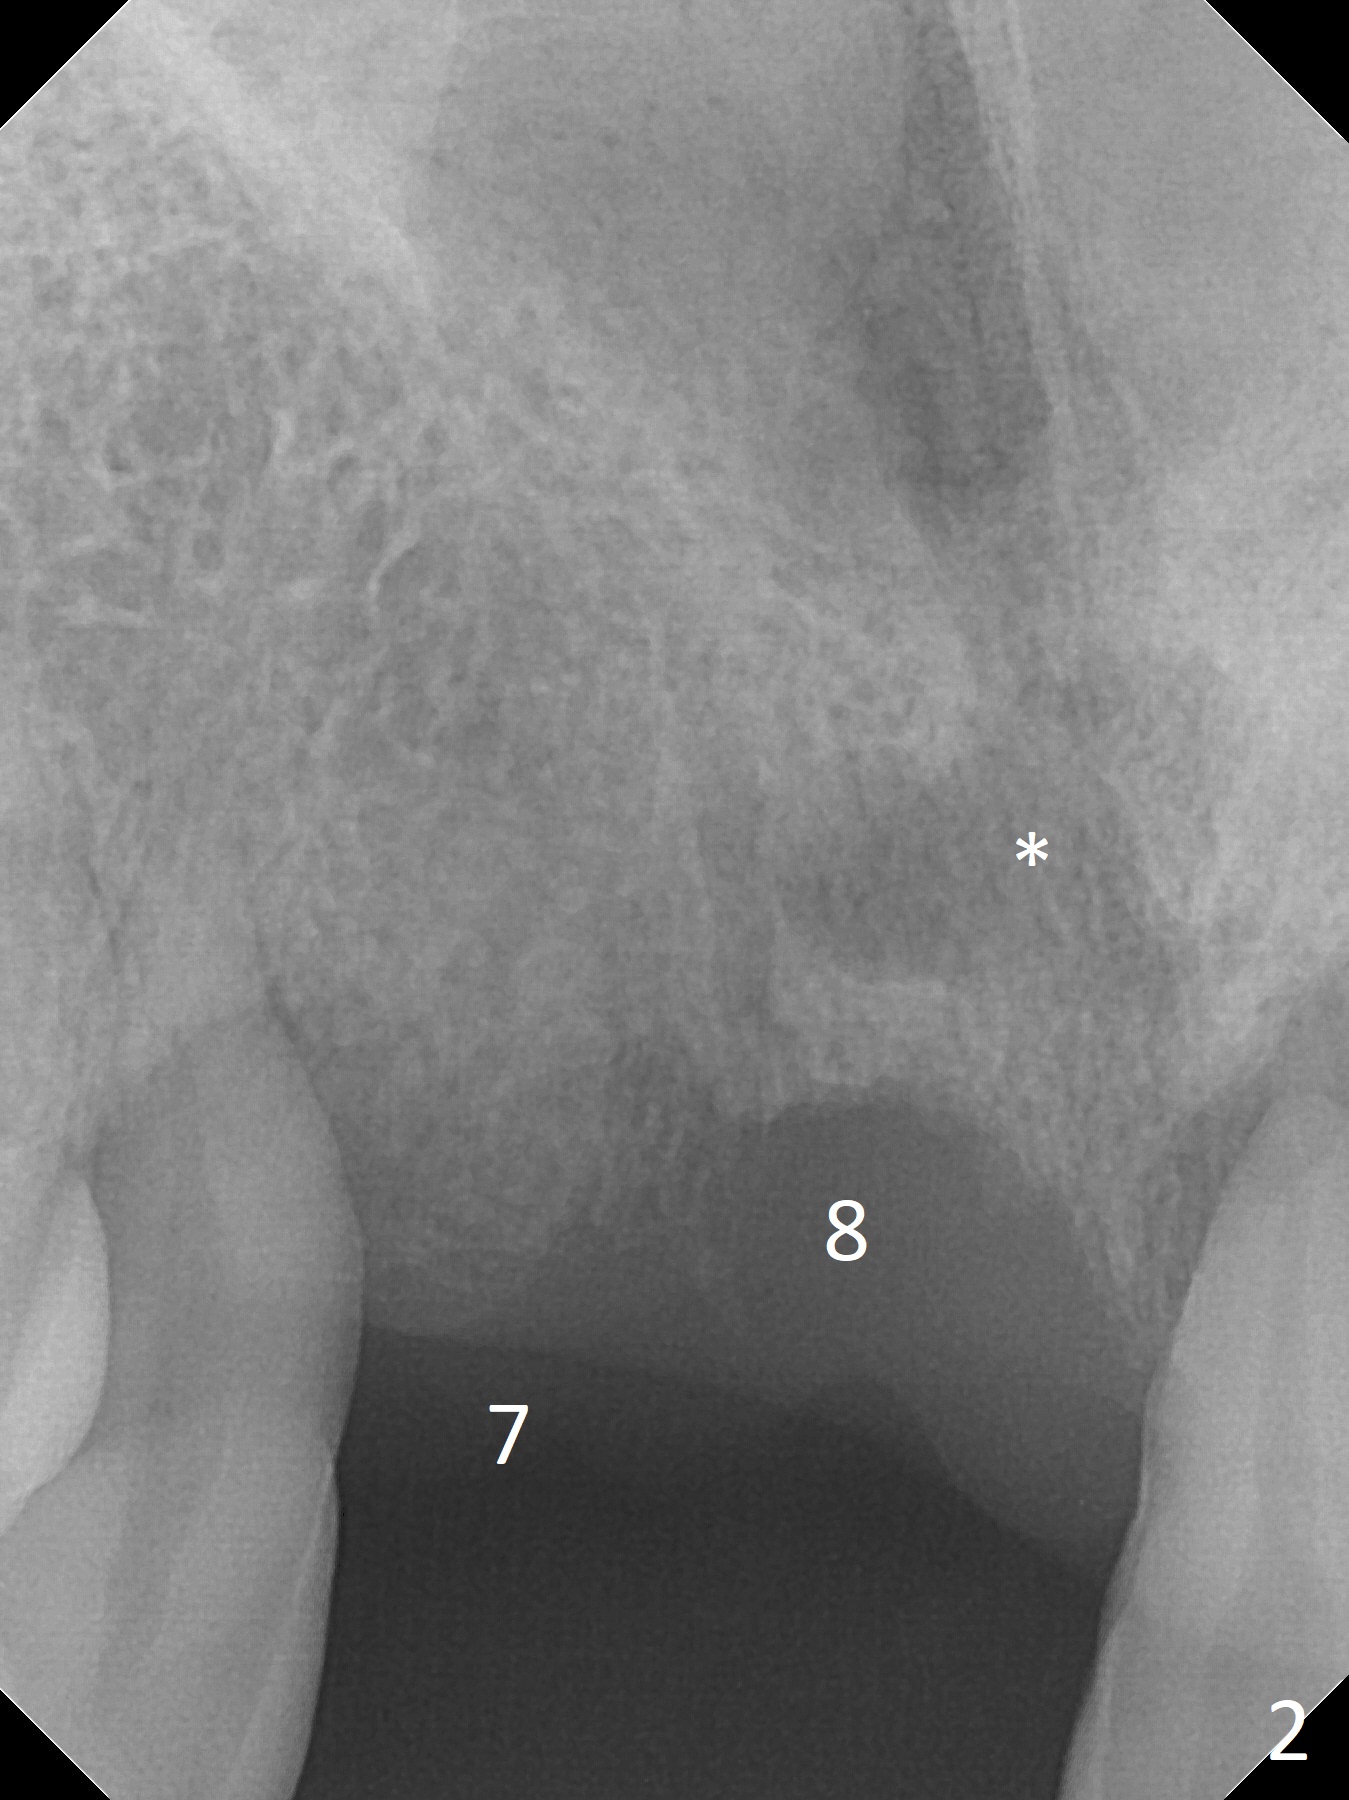

A 41-year-old woman returns to clinic with missing upper right incisors and mobile left ones (#9 fistula (Fig.1 *) 2 years post cementation of 23-25 implant FPD (Fig.2-3). The Incisive Canal is large (Fig.2,3 *). Place all of the 4 implants distally (2.5 or 3x10 or 12 mm (at 8,9), x12 or 14 mm (7,10)) and as deep as possible. The cuff is most likely 4 mm.